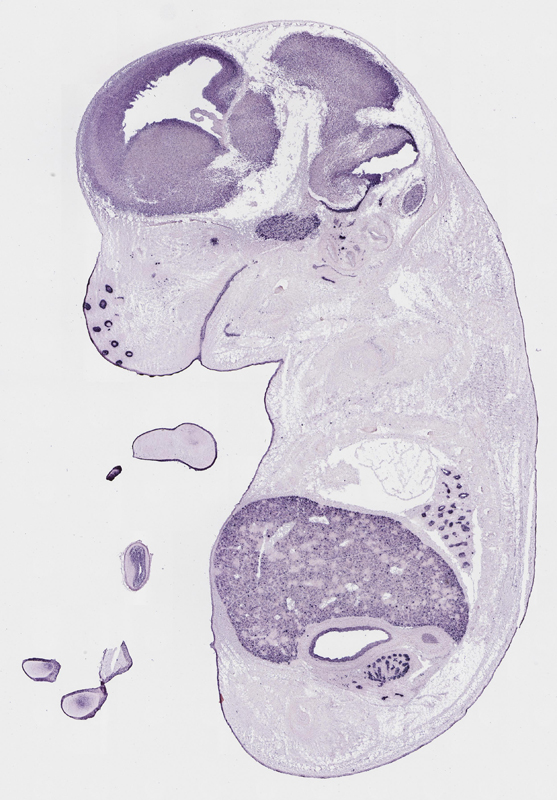

Specimen

euxassay_003287_01:

embryonic day 14.5